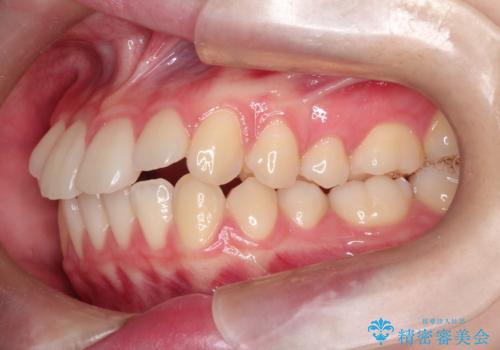

- 前歯のガタガタを主訴に来院されました。

開咬ぎみであったため、しっかりと前歯が噛むように計画を立てて治療をおこないました。

仕上がりも良く、患者様にも満足していただきました。